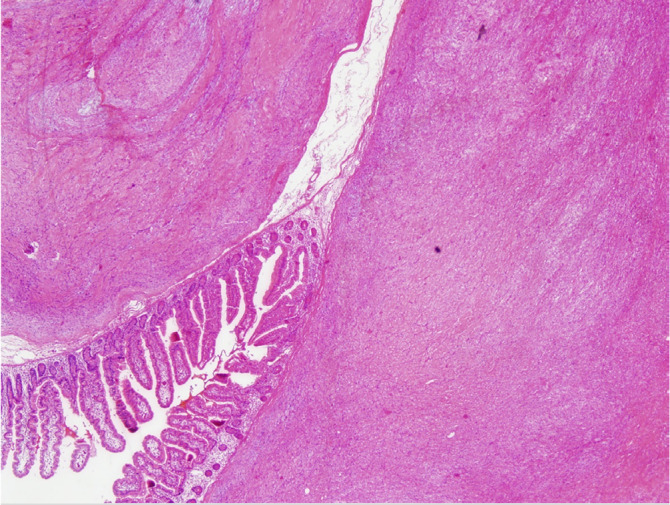

Gastrointestinal schwannomas are benign, slow-growing, rare tumors comprising 2-6% of all mesenchymal tumors of the gastrointestinal tract and 0.2% of all gastric neoplasms. In the gastrointestinal system, schwannomas are mostly observed in the stomach, followed by the colon and rectum. In this case series, we present the clinicopathological results of 9 cases, along with a literature review. A retrospective analysis was conducted on nine patients diagnosed with gastrointestinal schwannoma in a single institution. Tumors were located in the small intestine and stomach, with an average tumor size of 4.6 cm (range: 1.8-8.5 cm). Diagnoses were incidental in most cases, with only four patients presenting symptoms such as epigastric pain and changes in bowel habits. Histopathological characteristics of tumors were studied. Surgical resection with negative margins was performed in 8 cases. Histopathological analysis confirmed schwannomas characterized by solid, homogeneous, spindle-cell structures without cystic changes or necrosis. Immunohistochemically, all tumors were S-100 positive, with variable expression of other markers. Desmin was negative in seven samples. One gastric schwannoma showed focal smooth muscle actin positivity, while others were negative. The Ki-67 index ranged from 0% to 6%, and c-Kit was negative in all cases. DOG-1 expression was examined in four cases, showing focal positivity in small bowel schwannoma and negativity in three gastric schwannomas. Gastrointestinal schwannomas are predominantly benign tumors, more common in women, and typically occur in the sixth decade of life. While imaging and endoscopic techniques help in diagnosis, definitive diagnosis relies on histopathological analysis. Surgical resection remains the gold standard for treatment.